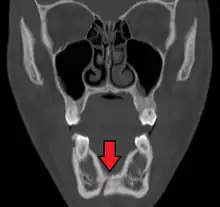

Towne's view of a bilateral condyle fracture. White arrow is a fracture on the neck of the condyle. Black arrow shows the condyle pulled to the medial. The same injury can be seen on the opposite side -